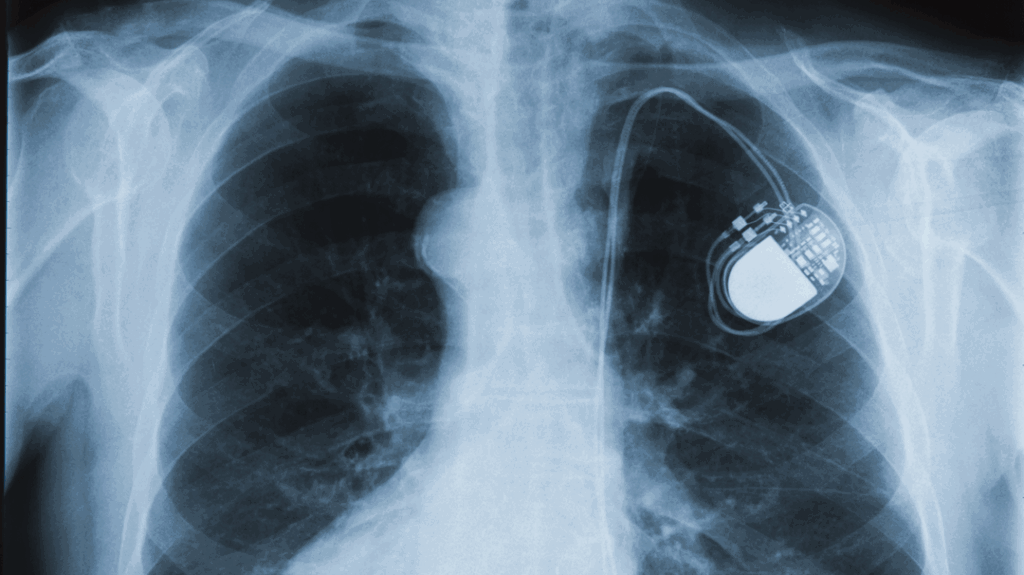

Pacemaker Chest X Ray Pacemakers And Emf Icds and pacemakers contain metal, and therefore, are not normally allowed near mri machines. Medical devices which use an energy source are known as active implantable medical devices (aimds). To date, there is no conclusive evidence for the extent to which sources of emf may cause harmful electromagnetic interference (emi) in patients with. The strong magnetic field can interfere with. Pacemakers And Emf.